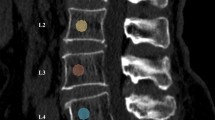

There is emerging evidence that radiomics analyses can improve detection of skeletal fragility. In this cross-sectional study, we evaluated radiomics features (RFs) on computed tomography (CT) images of the lumbar spine in subjects with or without fragility vertebral fractures (VFs).

Two-hundred-forty consecutive individuals (mean age 60.4 ± 15.4, 130 males) were evaluated by radiomics analyses on opportunistic lumbar spine CT. VFs were diagnosed in 58 subjects by morphometric approach on CT or XR-ray spine (D4-L4) images. DXA measurement of bone mineral density (BMD) was performed on 17 subjects with VFs.

Twenty RFs were used to develop the machine learning model reaching 0.839 and 0.789 of AUROC in the train and test datasets, respectively. After correction for age, VFs were significantly associated with RFs obtained from non-fractured vertebrae indicating altered trabecular microarchitecture, such as low-gray level zone emphasis (LGLZE) [odds ratio (OR) 1.675, 95% confidence interval (CI) 1.215–2.310], gray level non-uniformity (GLN) (OR 1.403, 95% CI 1.023–1.924) and neighboring gray-tone difference matrix (NGTDM) contrast (OR 0.692, 95% CI 0.493–0.971). Noteworthy, no significant differences in LGLZE (p = 0.94), GLN (p = 0.40) and NGDTM contrast (p = 0.54) were found between fractured subjects with BMD T score < − 2.5 SD and those in whom VFs developed in absence of densitometric diagnosis of osteoporosis.